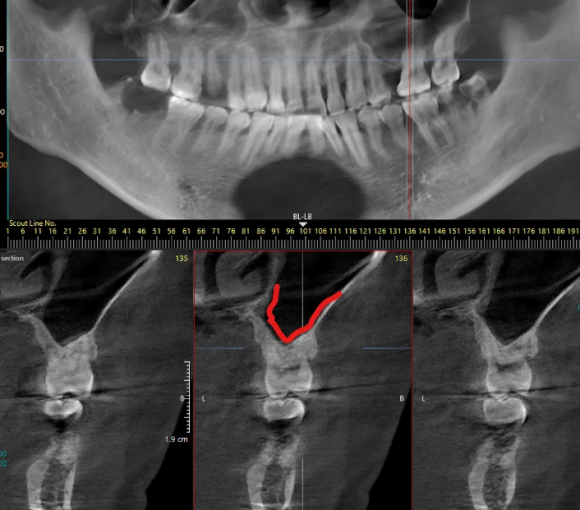

상악동 구조 파악을 위한 CT

또한 왼쪽 위 어금니는 발치 후 잇몸뼈가 부족뿐만 아니라, 상악동이라는 공기주머니와 가까운 위치에 있어 측면 접근법 상악동 거상술이라는 난도 높은 수술과 임플란트 골이식이 필요했는데요.

빨간선이 상악동 위치

이 과정은 상악동의 얇은 막을 조심스럽게 들어 올려 인공 뼈를 이식하는 매우 정교한 기술로 수술 경험과 전문성이 필요한 시술이지만,

구강외과 전문의가 월평균 352건의 수술을 진행하며 고난도 수술이 가능한 시스템을 갖추고 있어 도움을 드릴 수 있었습니다.

발치한 부위는 예상대로 뼈가 매우 얇아져 있어, 안정적인 인공치아 식립을 위해 뼈이식과 상악동 거상술을 병행했습니다.

상악동거상을 위해 측면 골을 열고 조심스럽게 올리는 모습

상악동 위치를 바꾸고 이공뼈 이식

임플란트 식립

특히 상악동에 가까운 부위에서는 공기주머니인 상악동 내부의 막을 들어 올리고 그 아래에 인공 뼈를 넣는 과정이 추가로 필요하기 때문에 경험과 해부학적 지식이 풍부한 구강외과 전문의가 시술하는 것을 추천해 드립니다.

상악동 위치

안정적으로 이식된 인공뼈

왼쪽 위 어금니는 발치 후 골이식과 상악동 거상술을 함께 시행했습니다.

수술 후 엑스레이에서 상악동이 인공 뼈로 채워진 모습이 확인되었고, 임플란트가 안정적으로 자리 잡았습니다.